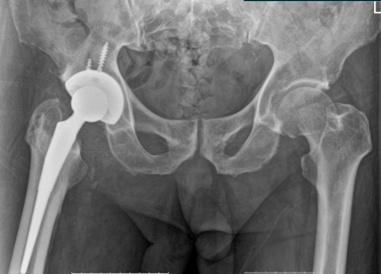

术前X光可见右髋关节骨性融合

有效解决髋关节僵硬这一难题的最好办法就是进行全髋关节置换术,然而长期丧失运动能力引起的骨质疏松及关节解剖结构的变异、关节长期强直软组织变性等一系列问题,致使手术难度大大增加。